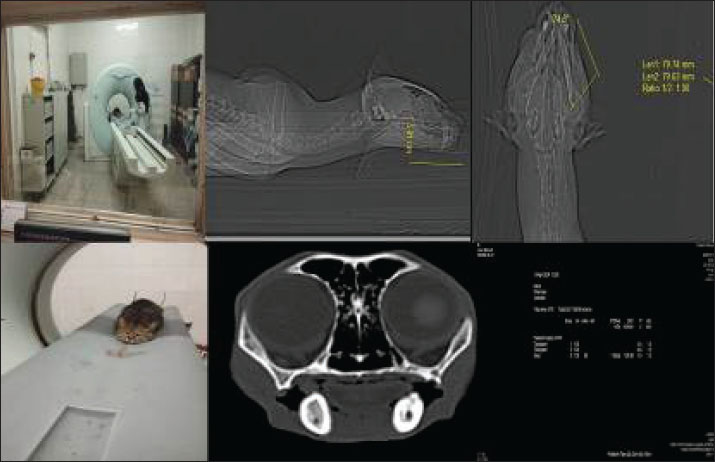

Fig. 1. High-resolution computed tomography imaging of a wild cat subject undergoing diagnostic evaluation for an oronasal fistula, highlighting the integration of advanced imaging modalities in preclinical research. This non-invasive approach enables precise fistula morphology assessment and anatomical mapping, thereby informing the development of bioengineered scaffolds and microbiome-targeted therapies to optimize wound closure and tissue regeneration.

Clinical examination and CT scan revealed an ONF measuring approximately 11 mm (caudal-to-rostral length) × 8 mm (width) at the level of the upper right canine, along with an OCF in the right lower canine tooth (Figs. 1 and 2) (Watanabe et al., 2022). Residual dentition included only the maxillary and mandibular incisors and second premolars, with no clinical evidence of gingivitis or periodontitis. Serological testing for Feline leukemia virus and Feline immunodeficiency virus yielded negative results (Little et al., 2011).